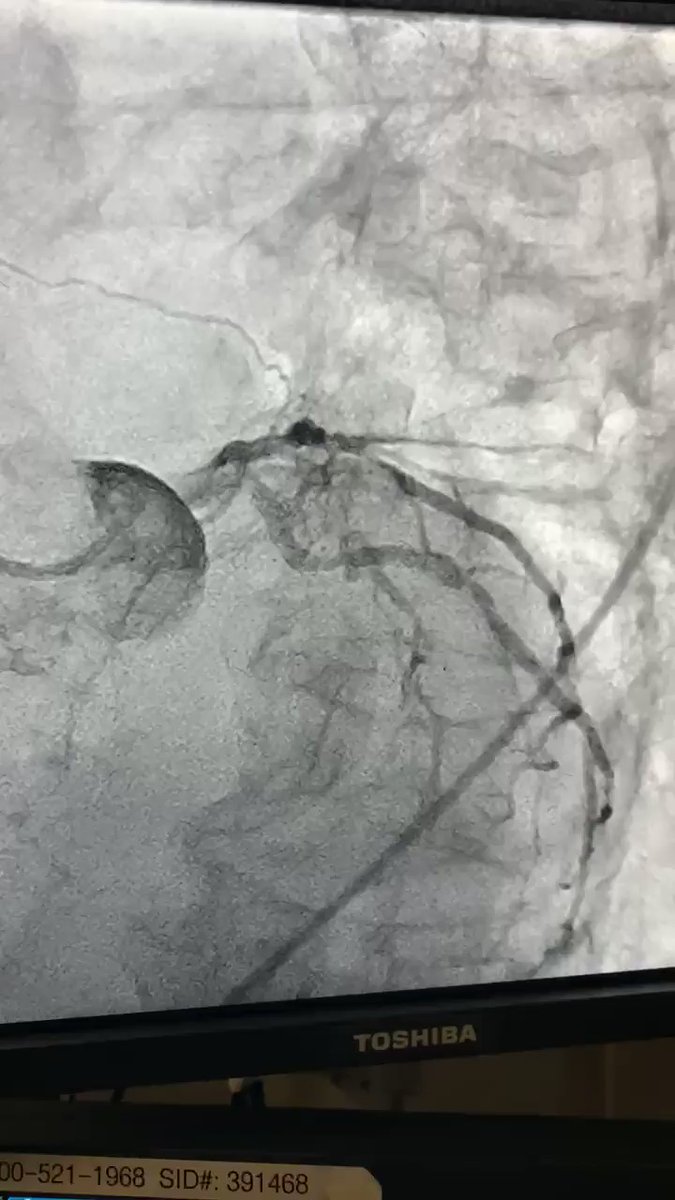

"89 yr old. NSTEMI. EF 25-30%. EDP 34. What would you do? @adnanalkhouli @GreggWStone @Drroxmehran @Cardiotweet @escardio @ACCinTouch"

(@JaffarRazaMD)